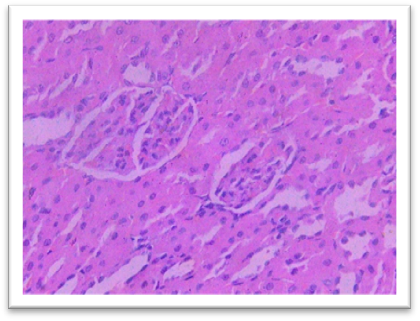

Histopathology

On day 42, rats were sacrificed for histopathological examination. Group I (Normal) and Group II (Lanthanum Carbonate only) showed normal kidney and liver architecture. Group III (Chronic Kidney Disease control) exhibited kidney damage, including crystals, congestion, haemorrhage, interstitial nephritis, and tubular dilatation. Group IV (Lanthanum Carbonate @150 mg/kg) showed moderate kidney fibrosis, mononuclear infiltration, and crystals. Group V (Lanthanum Carbonate @250 mg/kg) had mild fibrosis and sparse crystals. Group VI (Lanthanum Carbonate @500 mg/kg) showed minimal fibrosis and negligible crystals. Group VII (Lanthanum Carbonate @750 mg/kg) had minimal lesions with no crystals. Liver sections were normal in all groups. Histopathology studies revealed , The kidneys from a Chronic Kidney Disease (CKD) control rat (Group III) displayed significant macroscopic changes, including an increase in overall kidney size and the presence of multifocal, pinpoint, white granular raised lesions that were widely dispersed across the cortical surface. These observations are consistent with pathological alterations associated with CKD. Similar findings were reported by Yang et al. (2013) and Ali et al. (2015), who observed renal tissues exhibiting varying degrees of swelling and the presence of widespread white granular deposits on the cortical surfaces, consistent with the pathological features described in this study. Damment et al. (2011) observed significant changes in kidney architecture of Adenine induced Chronic Kidney Disease animals. The kidney from Group VII, treated with Lanthanum Carbonate @ 150mg/kg, 250mg/kg , 500mg/kg and 750 mg/kg body weight, demonstrated significant architectural improvement, along with a notable reduction in the number of crystalline deposits, indicating a substantial restoration of renal morphology and potential therapeutic efficacy at this dosage.

Fig 17 Group I Kidney showing normal histological architectural details under H & E 400 X.

Fig. 18 Group II Kidney showing histological details comparable with normal under 400 X